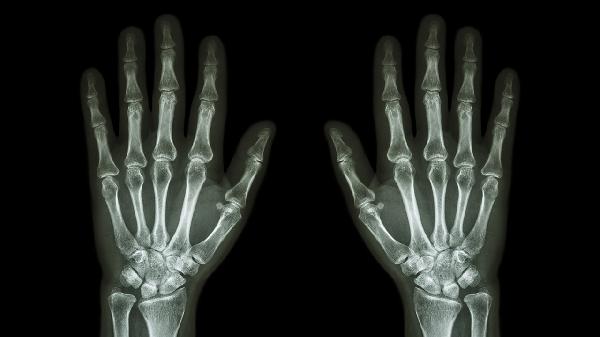

个别手指关节胀疼是什么原因

个别手指关节胀疼可能与关节劳损、骨关节炎、类风湿关节炎、痛风性关节炎、腱鞘炎等因素有关。建议及时就医明确病因,遵医嘱进行针对性治疗。

日常应注意避免手指长时间保持固定姿势,寒冷季节做好手部保暖。若疼痛持续超过两周、伴随关节变形或全身症状,需完善X线、类风湿因子等检查。饮食上适当增加富含欧米伽3脂肪酸的深海鱼类,控制精制糖和酒精摄入,肥胖者需减重以降低关节负荷。